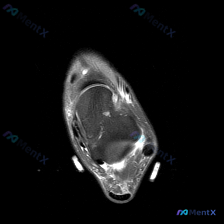

今天碰到一个有意思的读片矛盾病例,整理出来和大家分享一下思路。 病例基础信息 这是一张踝关节MRI T1加权轴位图像,用户观察到存在软组织液体,但单张影像读片结果如下: 1. 跟骨:骨髓脂肪信号均匀,皮质连续,未见骨质破坏、骨髓水肿或异常占位 2. 肌腱:胫骨后肌腱、趾长屈肌腱、𧿹长屈肌腱、腓骨长短...